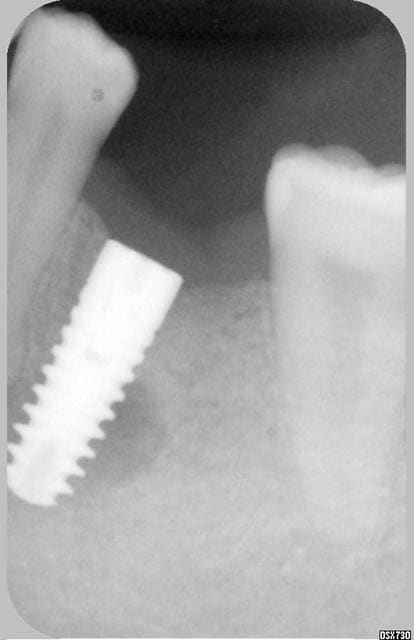

J'aimerai avoir votre avis sur ce cas (implant niveau 46).

L'image préop montrait déja une zone légèrement radioclaire.

celle-ci s'est "éclairci" sur le cliché à 3 mois, et est stable sur celui à 4 mois.

J'ai qd même posé aujourd'hui la vis de cicatrisation.

C'est complètement asymtômatique, trés stable, j'ai fait un essai de vissage d'un moignon à la clé dynamo et aucune douleur n'a été perçue.

Que faire ? attendre encore? poser la céram?

Image radioclaire et implant totalement immobile.

Six mois aprés la pose de la prothèse , implant toujours parfaitement immobile mais extériorisation vestibulaire d'une lésion de type granulomateuse.

Pour l'implant de rapeladent, je dirais que ça sent pas bon.

Fait un test au froid de la 45 pour voir si ton axe de forage n'a pas touché le paquet vasculonerveux de cette dent, ce qui pourrait expliquer effectivement la nécrose.

ca a l'air mal barre.

D'apres mon experience,lorsque tu as une image au tiers ou a "l'apex" de l'implant,et donc impossibilite de nettoyer,meme si l'implant semble solide (parceque qq mm du pas de vis sont osteointegres),eh bien le pronostique est plus que reserve.

L'axe est vraisemblablement incorrect, même si la "6" est versée en mésial...

L'image sombre autour de l'implant est comme une nuage noir qui préfigure l'orage... la "5" m'inquiète...